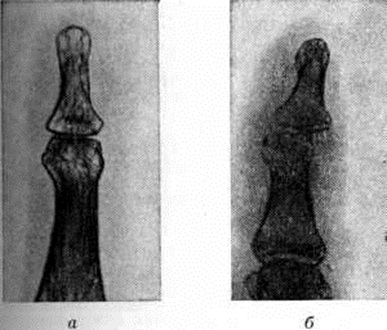

При костном панариции уже к концу 1-й недели болезни на рентгенограммах отмечается неравномерное просветление — реактивный остеопороз поражённой части фаланги вплоть до почти полного исчезновения структуры этой части фаланги при дальнейшем развитии Панариций (рисунок 6, а). По затихании воспаления очертания и структура фаланги восстанавливаются через 3—5 недель Ошибочное толкование этого просветления фаланги как некроза может привести к неоправданной резекции или даже экзартикуляции жизнеспособной фаланги. В отличие от описанной картины некротизированная часть фаланги, лишённая кровоснабжения, сохраняет на рентгенограммах тень нормальной интенсивности; образовавшийся секвестр часто смещается (рисунок 6, б). При интактности смежного сустава суставная щель и Подхрящевые корковые слои сохраняются. При осложнении костного Панариций гнойным артритом на рентгенограммах помимо остеопороза наблюдается прогрессирующее сужение суставной полости (вследствие хондролиза суставных хрящей), неровность и нечёткость контуров суставных концов (рисунок 7, а). Иногда гнойный артрит может осложниться дистензионным вывихом или подвывихом фаланги (рисунок 7, б).

Суставной Панариций ведёт к анкилозу; при этом на рентгенограмме исчезают корковые слои суставных концов и суставная полость, на месте которой костно-трабекулярная структура переходит из одной кости в другую. При активно и длительно текущем костном или суставном Панариций может наблюдаться просветление всех смежных костей кисти (главным образом суставных концов костей), то есть регионарный остеопороз. При костном Панариций дистальной фаланги на рентгенограммах отсутствует оссифицирующий периостит вследствие малой активности здесь камбиального, остеогенного слоя надкостницы.